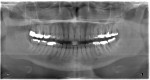

Even a seemingly well-completed root canal treatment (RCT) can fail if all of the pulpal tissue is not fully removed. In this case, the GentleWave® Procedure (Sonendo, Inc., gentlewave.com/doctor) was used to successfully retreat a failing traditional RCT. The GentleWave System is the first and only FDA-cleared system for RCT that addresses the limitations of conventional methods by combining procedure fluid optimization, broad-spectrum acoustic energy, and advanced fluid dynamics to debride and disinfect deep regions of the complex root canal system in a less-invasive procedure that preserves tooth structure. Tooth No. 19 was removed due to a fractured root prior to retreatment of tooth No. 18. The patient was administered anesthetic, and a rubber dam was placed for isolation. A conservative removal of the existing gutta-percha was accomplished using minimal rotary files. A SoundSeal® platform was constructed onto the tooth and treated with a CleanFlow™ procedure instrument (PI). The CleanFlow Technology cleans and disinfects without the PI entering the tooth. After 8 minutes and 15 seconds, the CleanFlow PI was removed and the canals dried. The molar system was filled to complete the retreatment in a single visit. Postoperative 2D and 3D radiographs demonstrated outstanding apical results. At the 1-month follow-up appointment, the patient reported no postoperative pain.